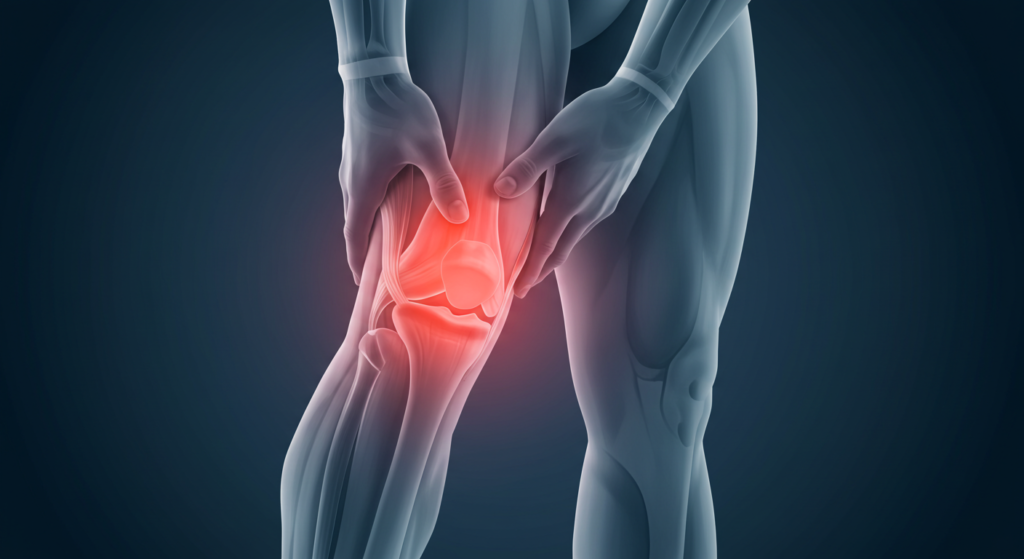

Sakit belakang lutut adalah masalah kesihatan yang sering dihadapi oleh ramai individu, terutamanya mereka yang aktif dalam sukan atau yang berusia. Sakit belakang lutut boleh menjadi sangat mengganggu dan mempengaruhi kualiti hidup secara keseluruhan. Kesakitan ini bukan sahaja boleh menghalang seseorang daripada melakukan aktiviti harian, tetapi juga boleh menyebabkan ketidakselesaan yang berpanjangan. Oleh itu, adalah penting untuk memahami punca-punca yang mungkin menyebabkan sakit belakang lutut agar langkah-langkah pencegahan dan rawatan yang sesuai dapat diambil.

Terdapat pelbagai punca yang boleh menyebabkan sakit belakang lutut. Salah satu punca yang paling biasa adalah kecederaan akibat aktiviti fizikal yang berlebihan, terutamanya dalam kalangan atlet atau individu yang terlibat dalam sukan. Kecederaan seperti ligamen terkoyak, tendonitis, atau kerosakan pada tulang rawan boleh menyebabkan sakit belakang lutut yang ketara. Selain itu, masalah perubatan seperti arthritis juga boleh menjadi penyebab sakit belakang lutut, di mana keradangan pada sendi boleh menyebabkan kesakitan dan kekakuan.

Untuk mengenal pasti jenis masalah yang mungkin anda hadapi, adalah penting untuk memerhatikan gejala yang menyertai sakit belakang lutut. Jika sakit belakang lutut disertai dengan bengkak, kemerahan, atau kesukaran untuk bergerak, ini mungkin menunjukkan kecederaan yang lebih serius. Dalam kes seperti ini, mendapatkan nasihat daripada pakar perubatan adalah langkah yang bijak. Mereka dapat melakukan pemeriksaan fizikal dan mungkin mencadangkan ujian lanjut seperti imbasan MRI untuk menentukan punca sebenar sakit belakang lutut yang anda alami.

Sebelum kita membincangkan sama ada sakit lutut adalah hasil daripada kecederaan atau masalah perubatan, adalah penting untuk memahami beberapa punca yang mungkin menyumbang kepada kesakitan ini. Sakit belakang lutut boleh disebabkan oleh pelbagai faktor, dan mengenal pasti punca-punca ini adalah langkah pertama dalam mendapatkan rawatan yang sesuai.

Kecederaan adalah salah satu punca utama, terutamanya bagi mereka yang terlibat dalam aktiviti fizikal yang intensif. Kecederaan ligamen, tendon, atau otot di sekitar lutut boleh menyebabkan sakit lutut yang ketara. Sebagai contoh, seorang atlet yang mengalami kecederaan ligamen semasa bermain bola sepak mungkin merasakan kesakitan yang tajam di belakang lutut mereka. Kecederaan ini boleh berlaku akibat pergerakan yang tiba-tiba, seperti melompat atau mengubah arah dengan cepat, yang menyebabkan tekanan berlebihan pada lutut.

Di samping itu, masalah perubatan seperti arthritis juga boleh menjadi punca sakit belakang lutut. Arthritis adalah penyakit radang sendi yang menyebabkan keradangan dan kesakitan pada sendi. Terdapat beberapa jenis arthritis, tetapi osteoarthritis adalah yang paling biasa berlaku, terutamanya di kalangan individu yang lebih tua. Osteoarthritis boleh menyebabkan tulang rawan di sendi lutut menjadi haus dan rosak, yang seterusnya menyebabkan kesakitan yang berterusan.